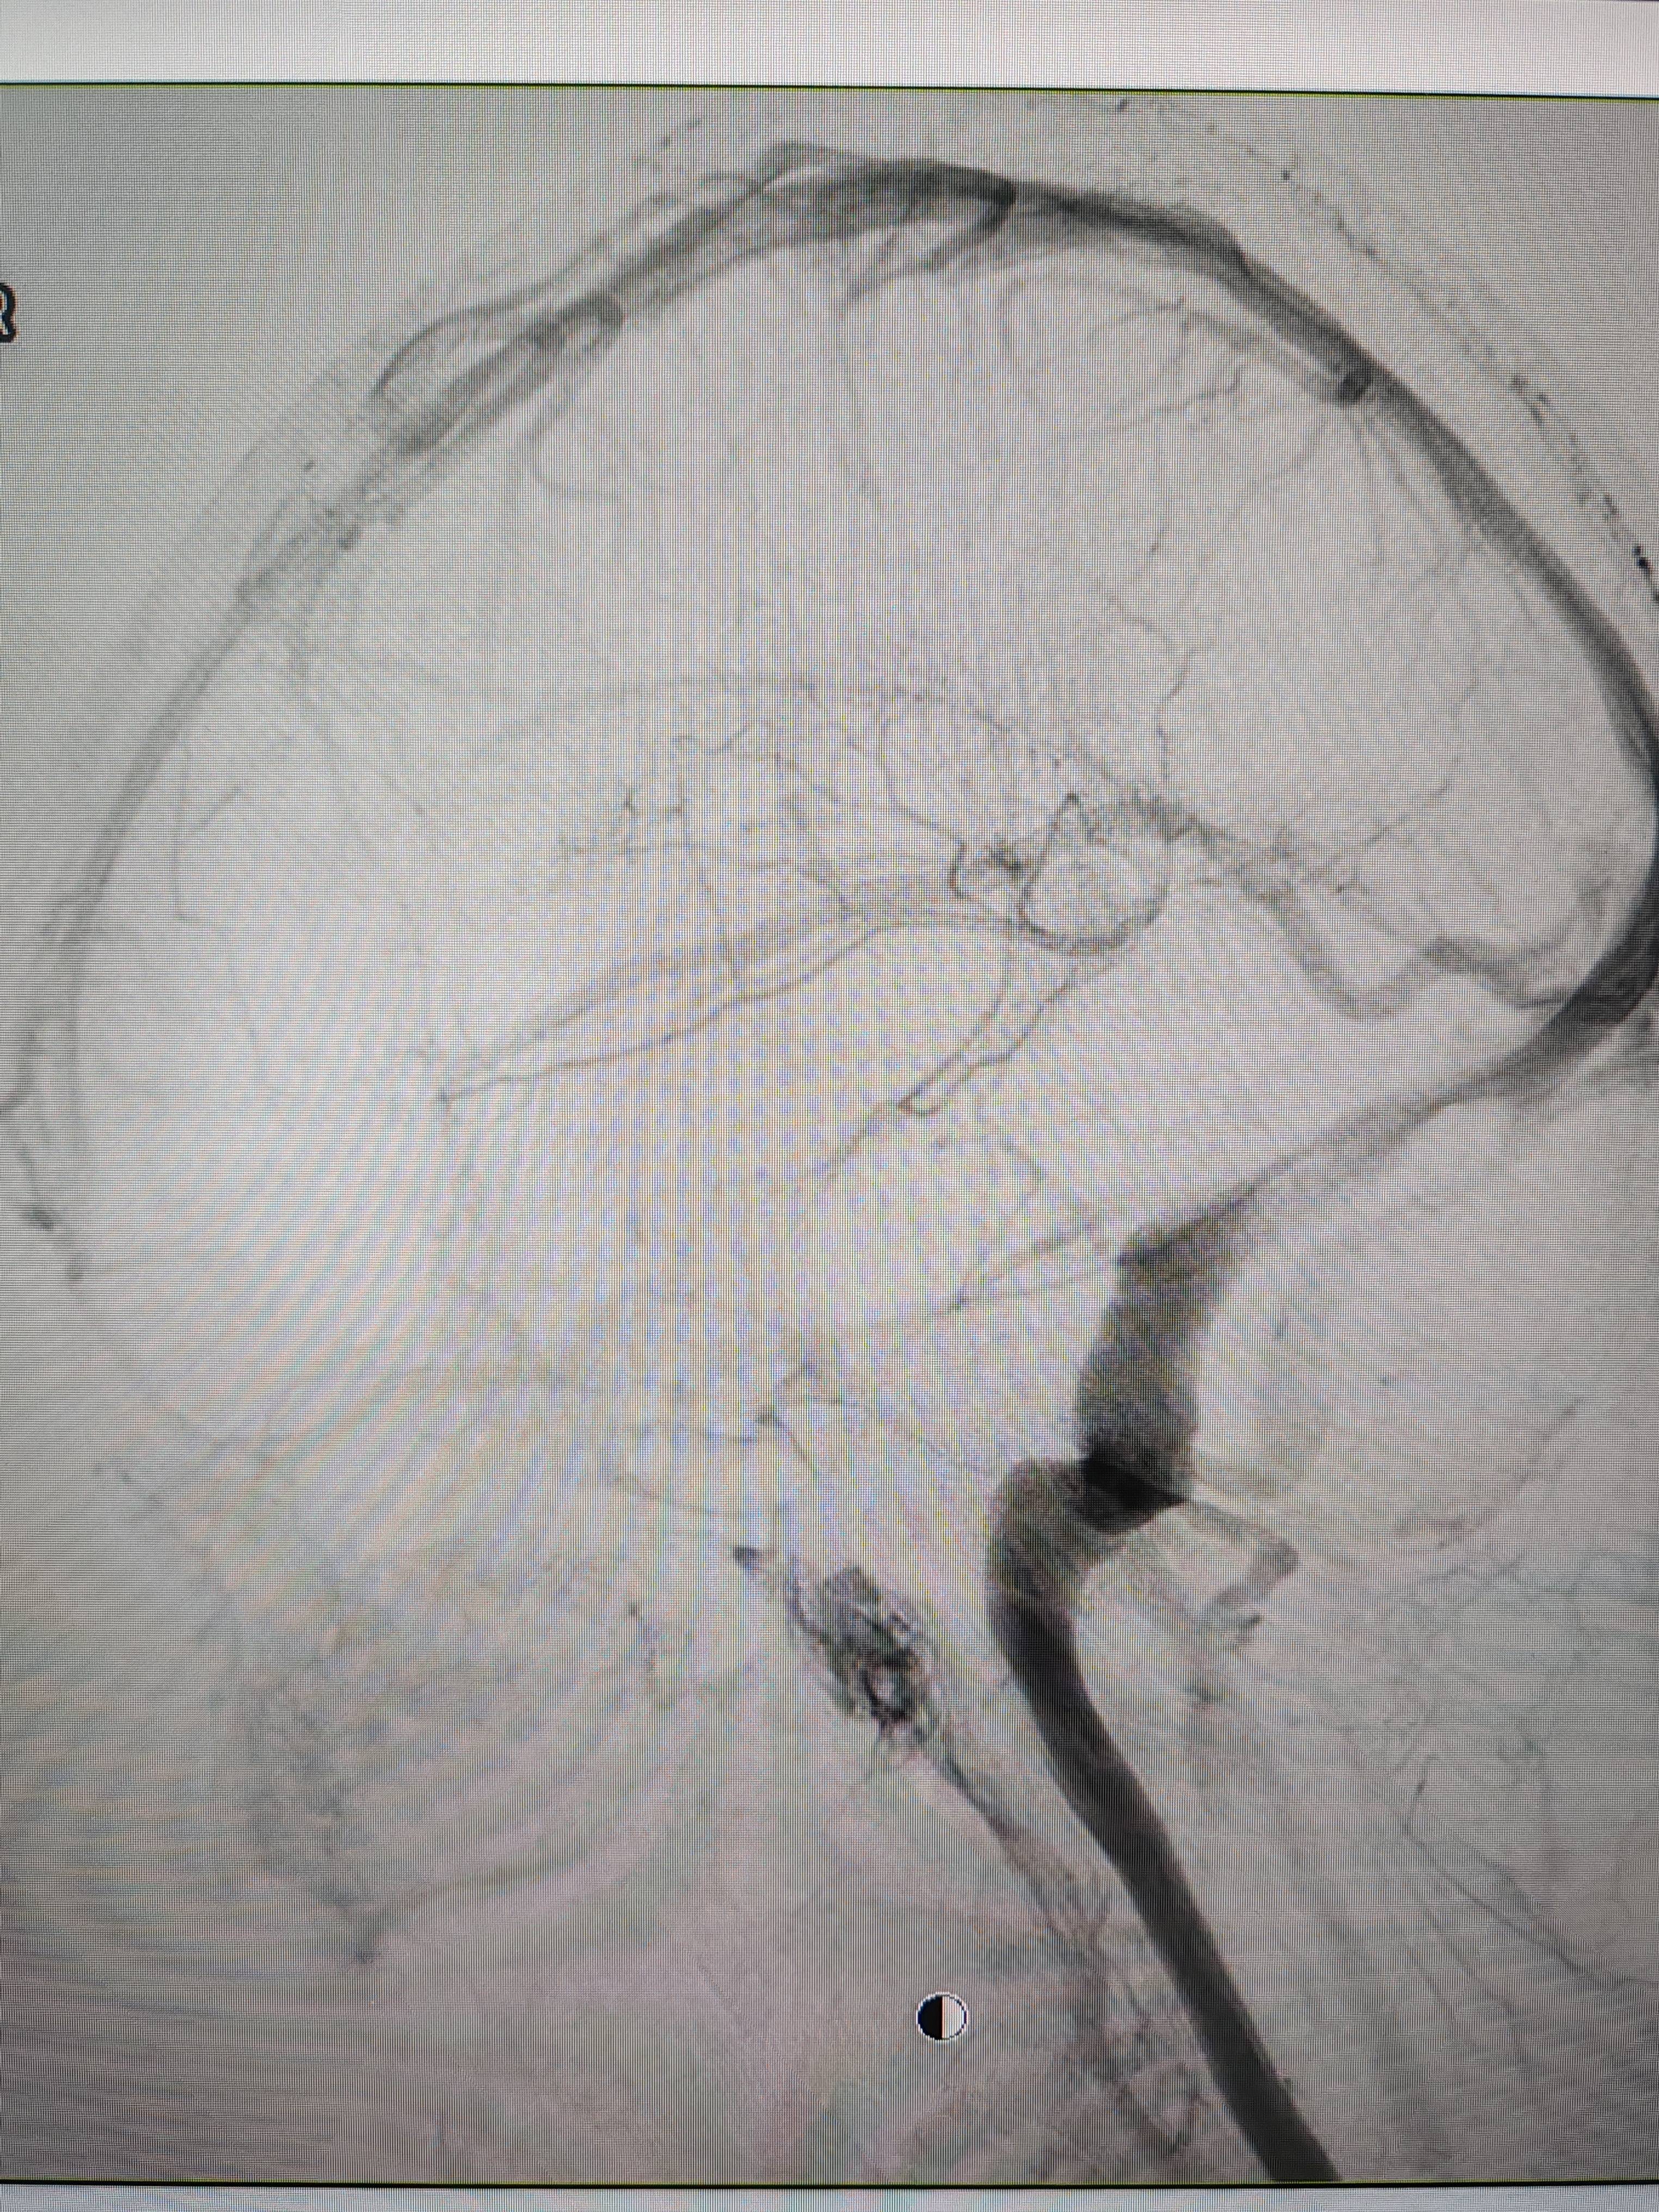

患者造影图像显示,其耳侧静脉窦狭窄初入币圈。 南方+ 欧阳少伟 拍摄

李宝民举例说,通过查体、CT、造影等影像技术的检查,患者赵女士是由于静脉窦狭窄,导致缓慢的静脉血流也出现“湍流”现象,其拐弯、打漩涡、回流产生的声响,又顺着骨传导,传至耳蜗处,进而让患者出现搏动性耳鸣的症状初入币圈